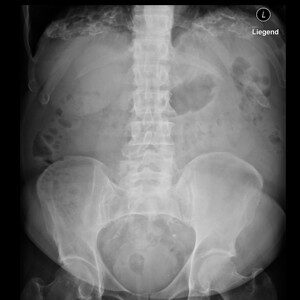

Reale Klinikbilder statt Demo-Grafiken.

Die spezialisierte Lernplattform für Projektionsradiographie. Im Mitgliederbereich steht eine stetig wachsende Fallsammlung mit realen Röntgenbildern zur Verfügung — systematisch aufgebaut, mit strukturierter Befundung, Befundcheck und klinisch relevanten Zusatzhinweisen.